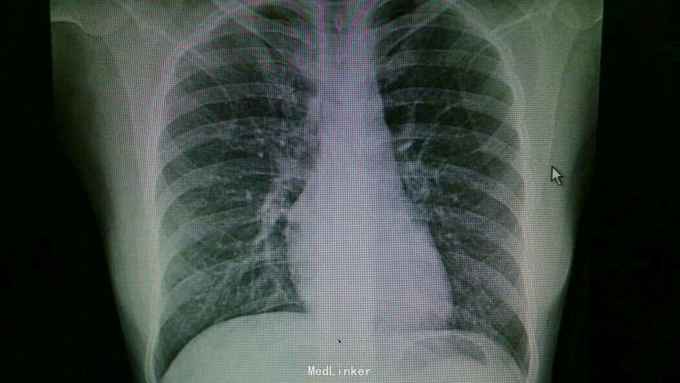

主诉:咽痛,咳嗽1周余。 病史:患者1周前出现咽痛,咳嗽,伴有咳痰,为黄色粘稠痰,当时有发热,最高体温37.6摄氏度,伴有畏寒,寒战,余无不适就诊。

查体:双肺呼吸音粗,右肺可闻及湿罗音, 余无特殊 辅查:血常规示中性粒细胞稍高。胸片:右上肺野炎性病变。肺炎支原体抗体滴度1:640。胸部CT:双肺炎症。

诊断:支原体肺炎。 治疗,予以阿奇霉素抗感染,止咳化痰等处理。复查胸片提示炎症较前好转。